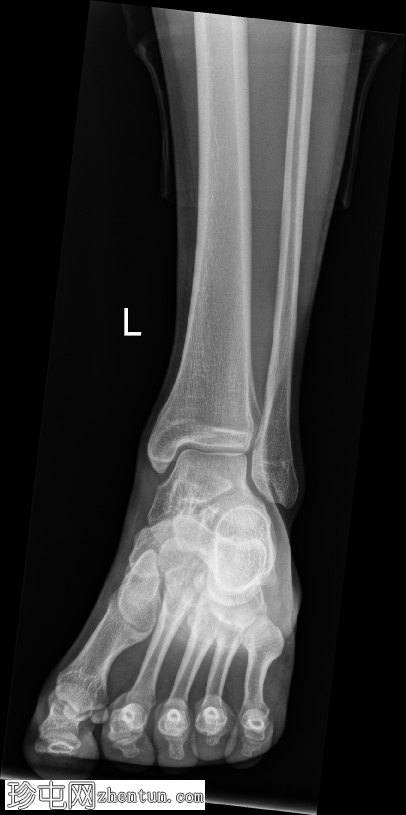

正位片

可见舟骨旁有一块骨化的舟上骨,符合副骨的特征。

此外,舟骨背侧可见一小块不规则且骨化不良的骨碎片,提示舟骨撕脱性骨折。踝关节前侧软组织肿胀,提示可能伴有软组织损伤。